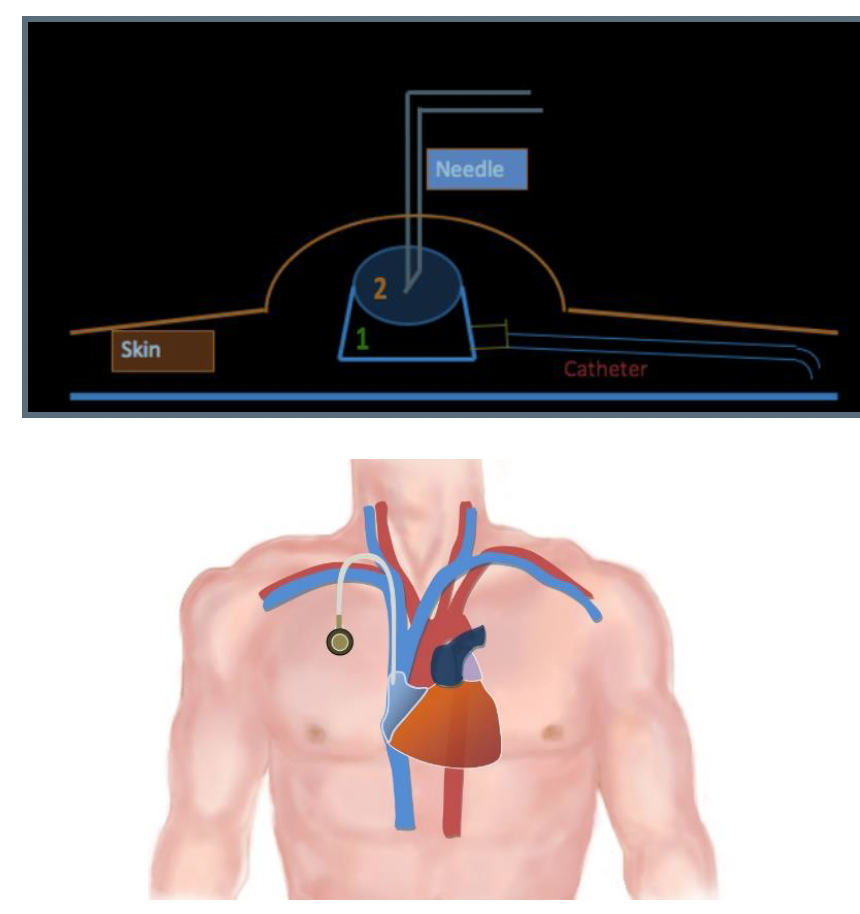

A chemoport, or central venous port (CVP), is a venous access device that is entirely implanted under the skin, most commonly on the anterior chest wall1 (Figure 1). The first report of subcutaneous tunneled CVP placement in 19822 was described by a surgeon, and the first successful radiologically inserted chemoport was reported by Morris et al3 in 1992. Since then, chemoports have been widely used in treating oncology patients requiring repeated intravenous administration of chemotherapy as they provide long-term venous access that is safe, easy, durable, and cosmetically accepted by oncology patients.4,5